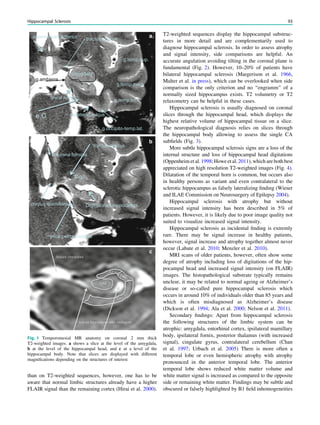

Fig. 1 Digital photogram of the brain surface before placement of a

subdural 8 9 8 grid. A second photogram was taken after grid

placement and digitally replaced by a schematic drawing detailing the

results of electrical stimulations and ictal/ intraictal EEG activity. Blue

grid contacts represent the eloquent zone, which is the motor cortex in

this case. The black area represents the epileptogenic lesion, defined

as the radiographic lesion that causes the seizures. The yellow area is

the seizure onset zone, defined as the area from which the clinical

seizures are generated. The seizure onset zone is often, but not

necessarily, congruent with the epileptogenic zone, defined as the

cortex area indispensable for the generation of seizures